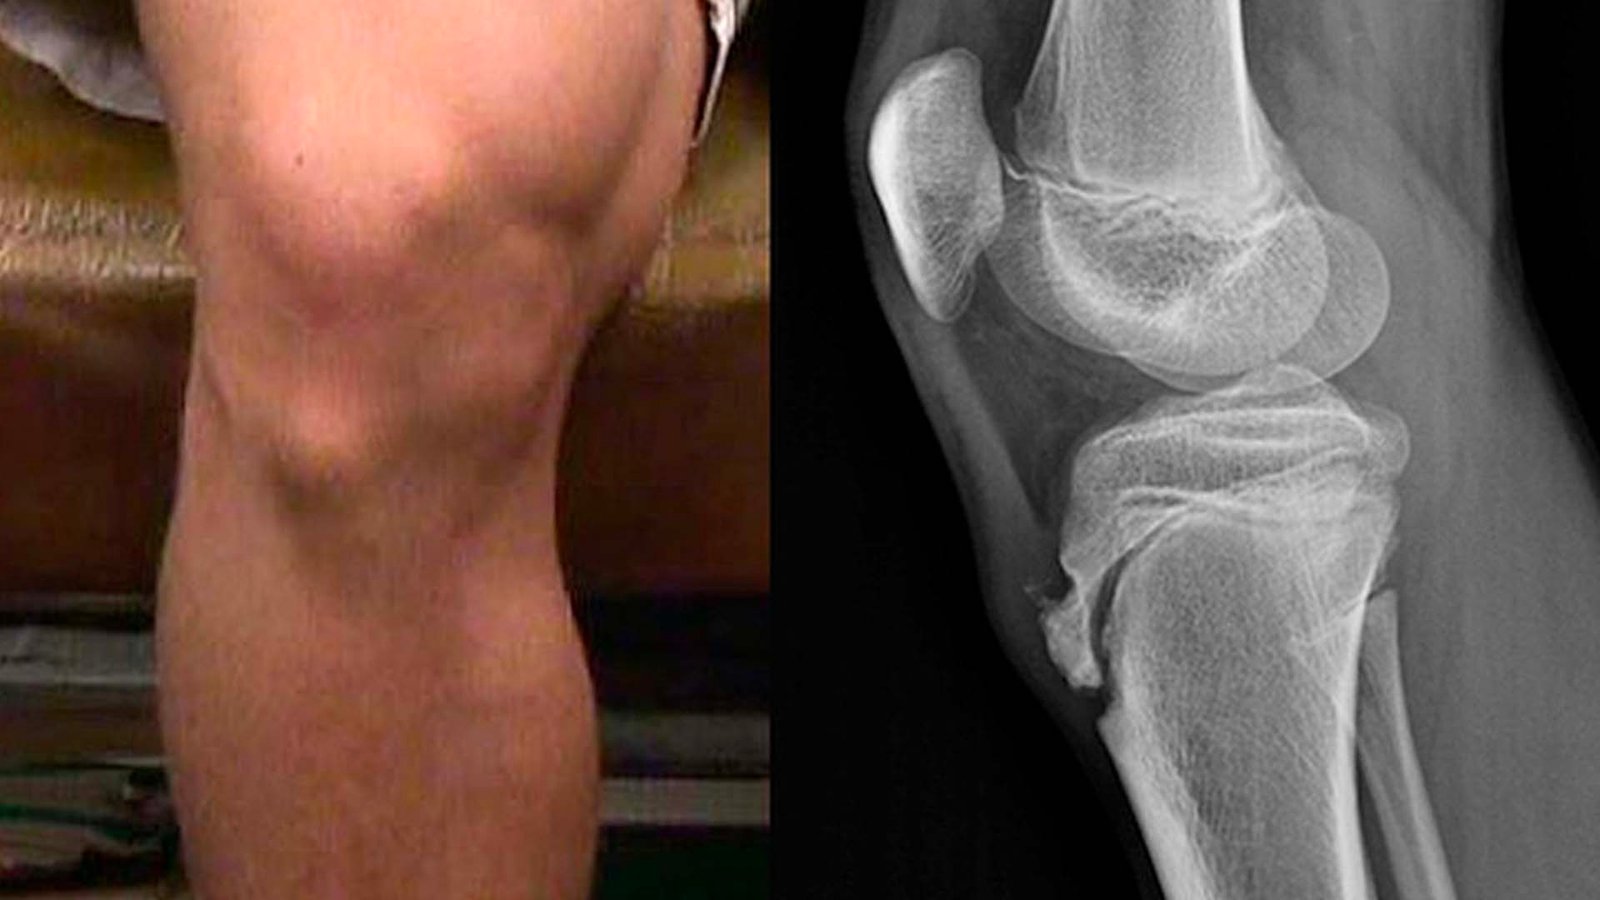

Симптоми, Або Як Упізнати Такий Стан

- Набряк під колінною чашечкою – часто можна навіть намацати.

- Невеликі виступи на кістці, які нагадують тобі, що життя – нерівномірна дорога.

Діагностика: не все так просто

Ви гадаєте, що просто аналізи треба здавати, аби зрозуміти, що з вами відбувається? Пошліться. В цьому випадку вирішує багато чинників. Лікарі зазвичай проводять фізичне обстеження, можуть також направити на рентген для чіткішої картини, щоб оцінити стан кісток. Іноді повний набір даних допомагає виявити приховану частинку пазла.